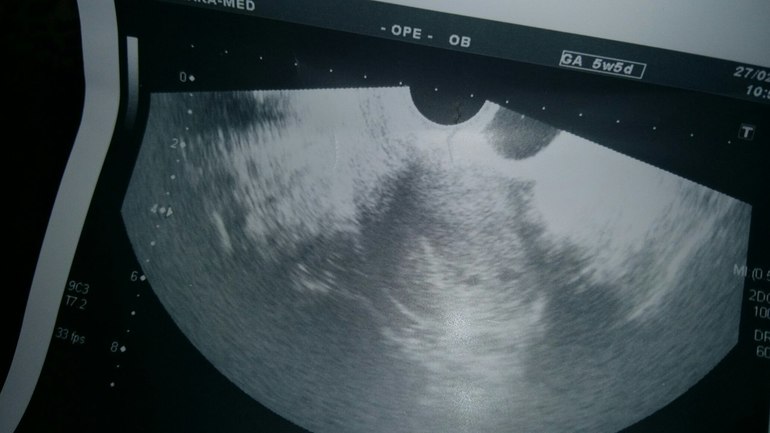

Сегодня были мы на УЗИ, новости и хорошие и плохие, далее под кат-много букв...

Новость первая-беременность есть и она маточная.Новость вторая- под вопросом двойня... Фото с УЗИ прилагаю, думаю, рано еще о чем-то говорить. Вы как думаете, что видите? Врач сказала, что ей самой интересно и контроль через 10 дней. Новость третья- не очень хорошая- поставила угрозу. Вот глядя на снимок, не могу понять, как и где она это определила... в итоге назначили Фемибион 1, Магне б6, Дюфастон аж 4 табл. в день, не много ли ???. Так не хочется мне на таблетках сидеть. а если вдруг что... ТТТ. может угроза из-за того, что дочку много таскаю... Что делать, не знаю...

У меня, кстати, тоже сначала подозрение на двойню было, ХГЧ очень высокий и рос в 4 раза за 2 дня, но плодное яйцо одно было, правда очень большое. Сказали, что, скорее всего "рассосался" один, чтобы другому дать питаться. А у вас очень похоже, что 2 плодных яйца)))))

Дочка у вас уже большая, отучайте от рук, на улице коляску, дома табуретка и.т.д. Ну и отдыхайте побольше, а таблетки, ну и ладно, главное чтобы никаких угроз не было. Фото с узи, прям ми ми ми, две точечьки), пусть это будет здоровая двойня)